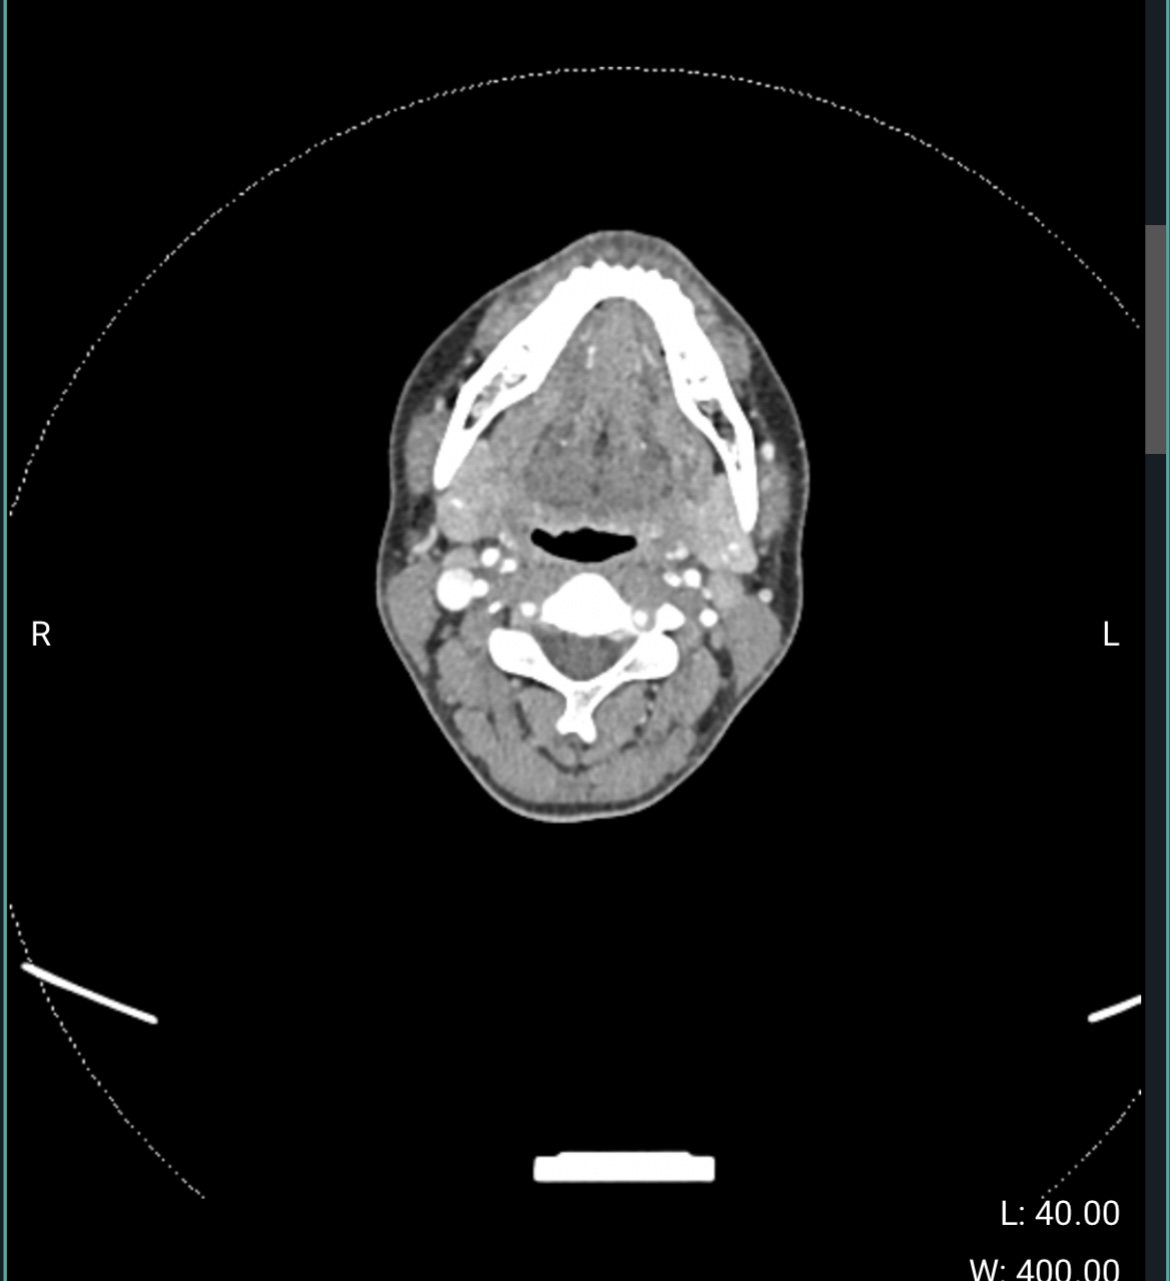

@Coco1 If you go into the axial view of your CT imaging I can help you locate the hyoid bone to see if the greater horns are contributing to any of your symptoms.

See attached some examples to help you locate it. It will look like a horseshoe. Sometimes the whole hyoid can be seen in one slice, but often the greater horns are slightly higher since the hyoid is typically angled. The greater horns are what we are interested in seeing.

Thank you so much! Is this helpful at all lol? I have no idea what I am doing :sweat_smile:

Is this a CT with contrast? If so, odd that the soft tissues, arteries, and veins are all the same shade grey?

Ahh sorry these were from my normal ct…these are the contrast ones…

@Coco1 can you go up a slice or two from this image and follow the bones until you come to the ends of them? Should be one or two slices id imagine.

Sorry, really appreciate your help! Not sure if I did it right…

@Coco1 see attached your annotated imaging.

Looks like your greater horns are in the clear, if that’s what I’m seeing. I labeled your ECAs, but less confident in labeling your IJVs and ICAs because one of them on the left side looks to be missing contrast at this level.